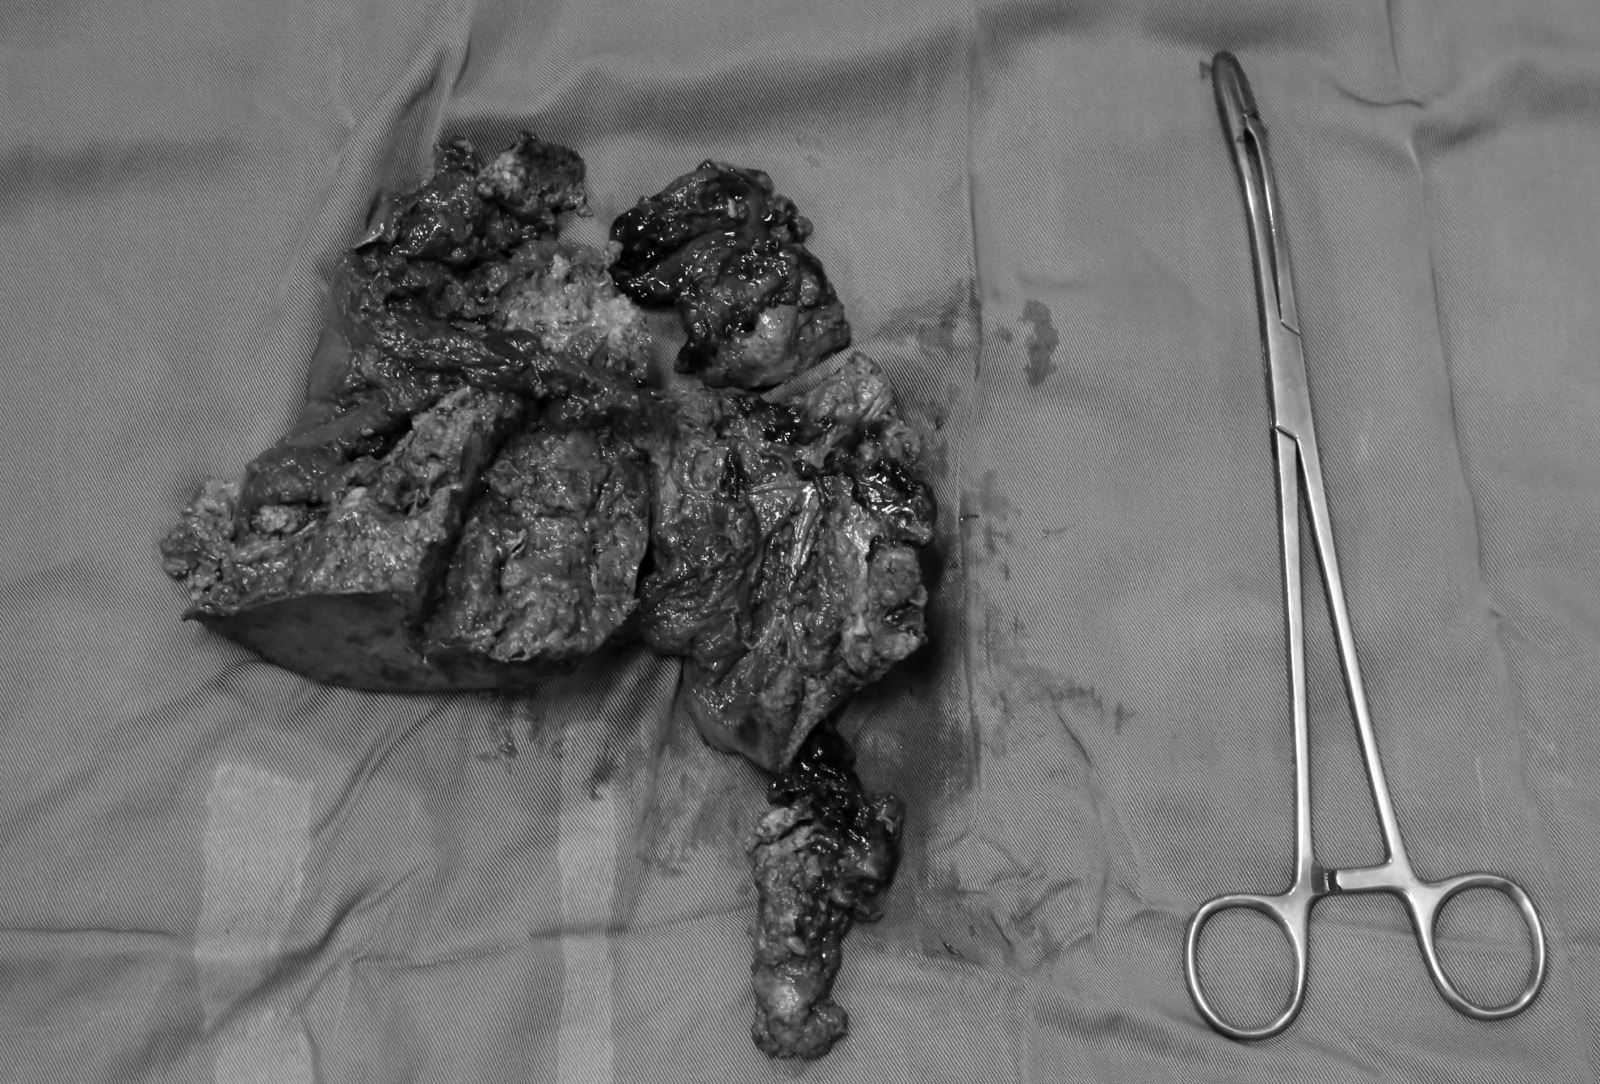

Phần gan bị dập nát phức tạp được xử trí cắt bỏ.

Phần gan bị dập nát đã được cắt bỏ an toàn.